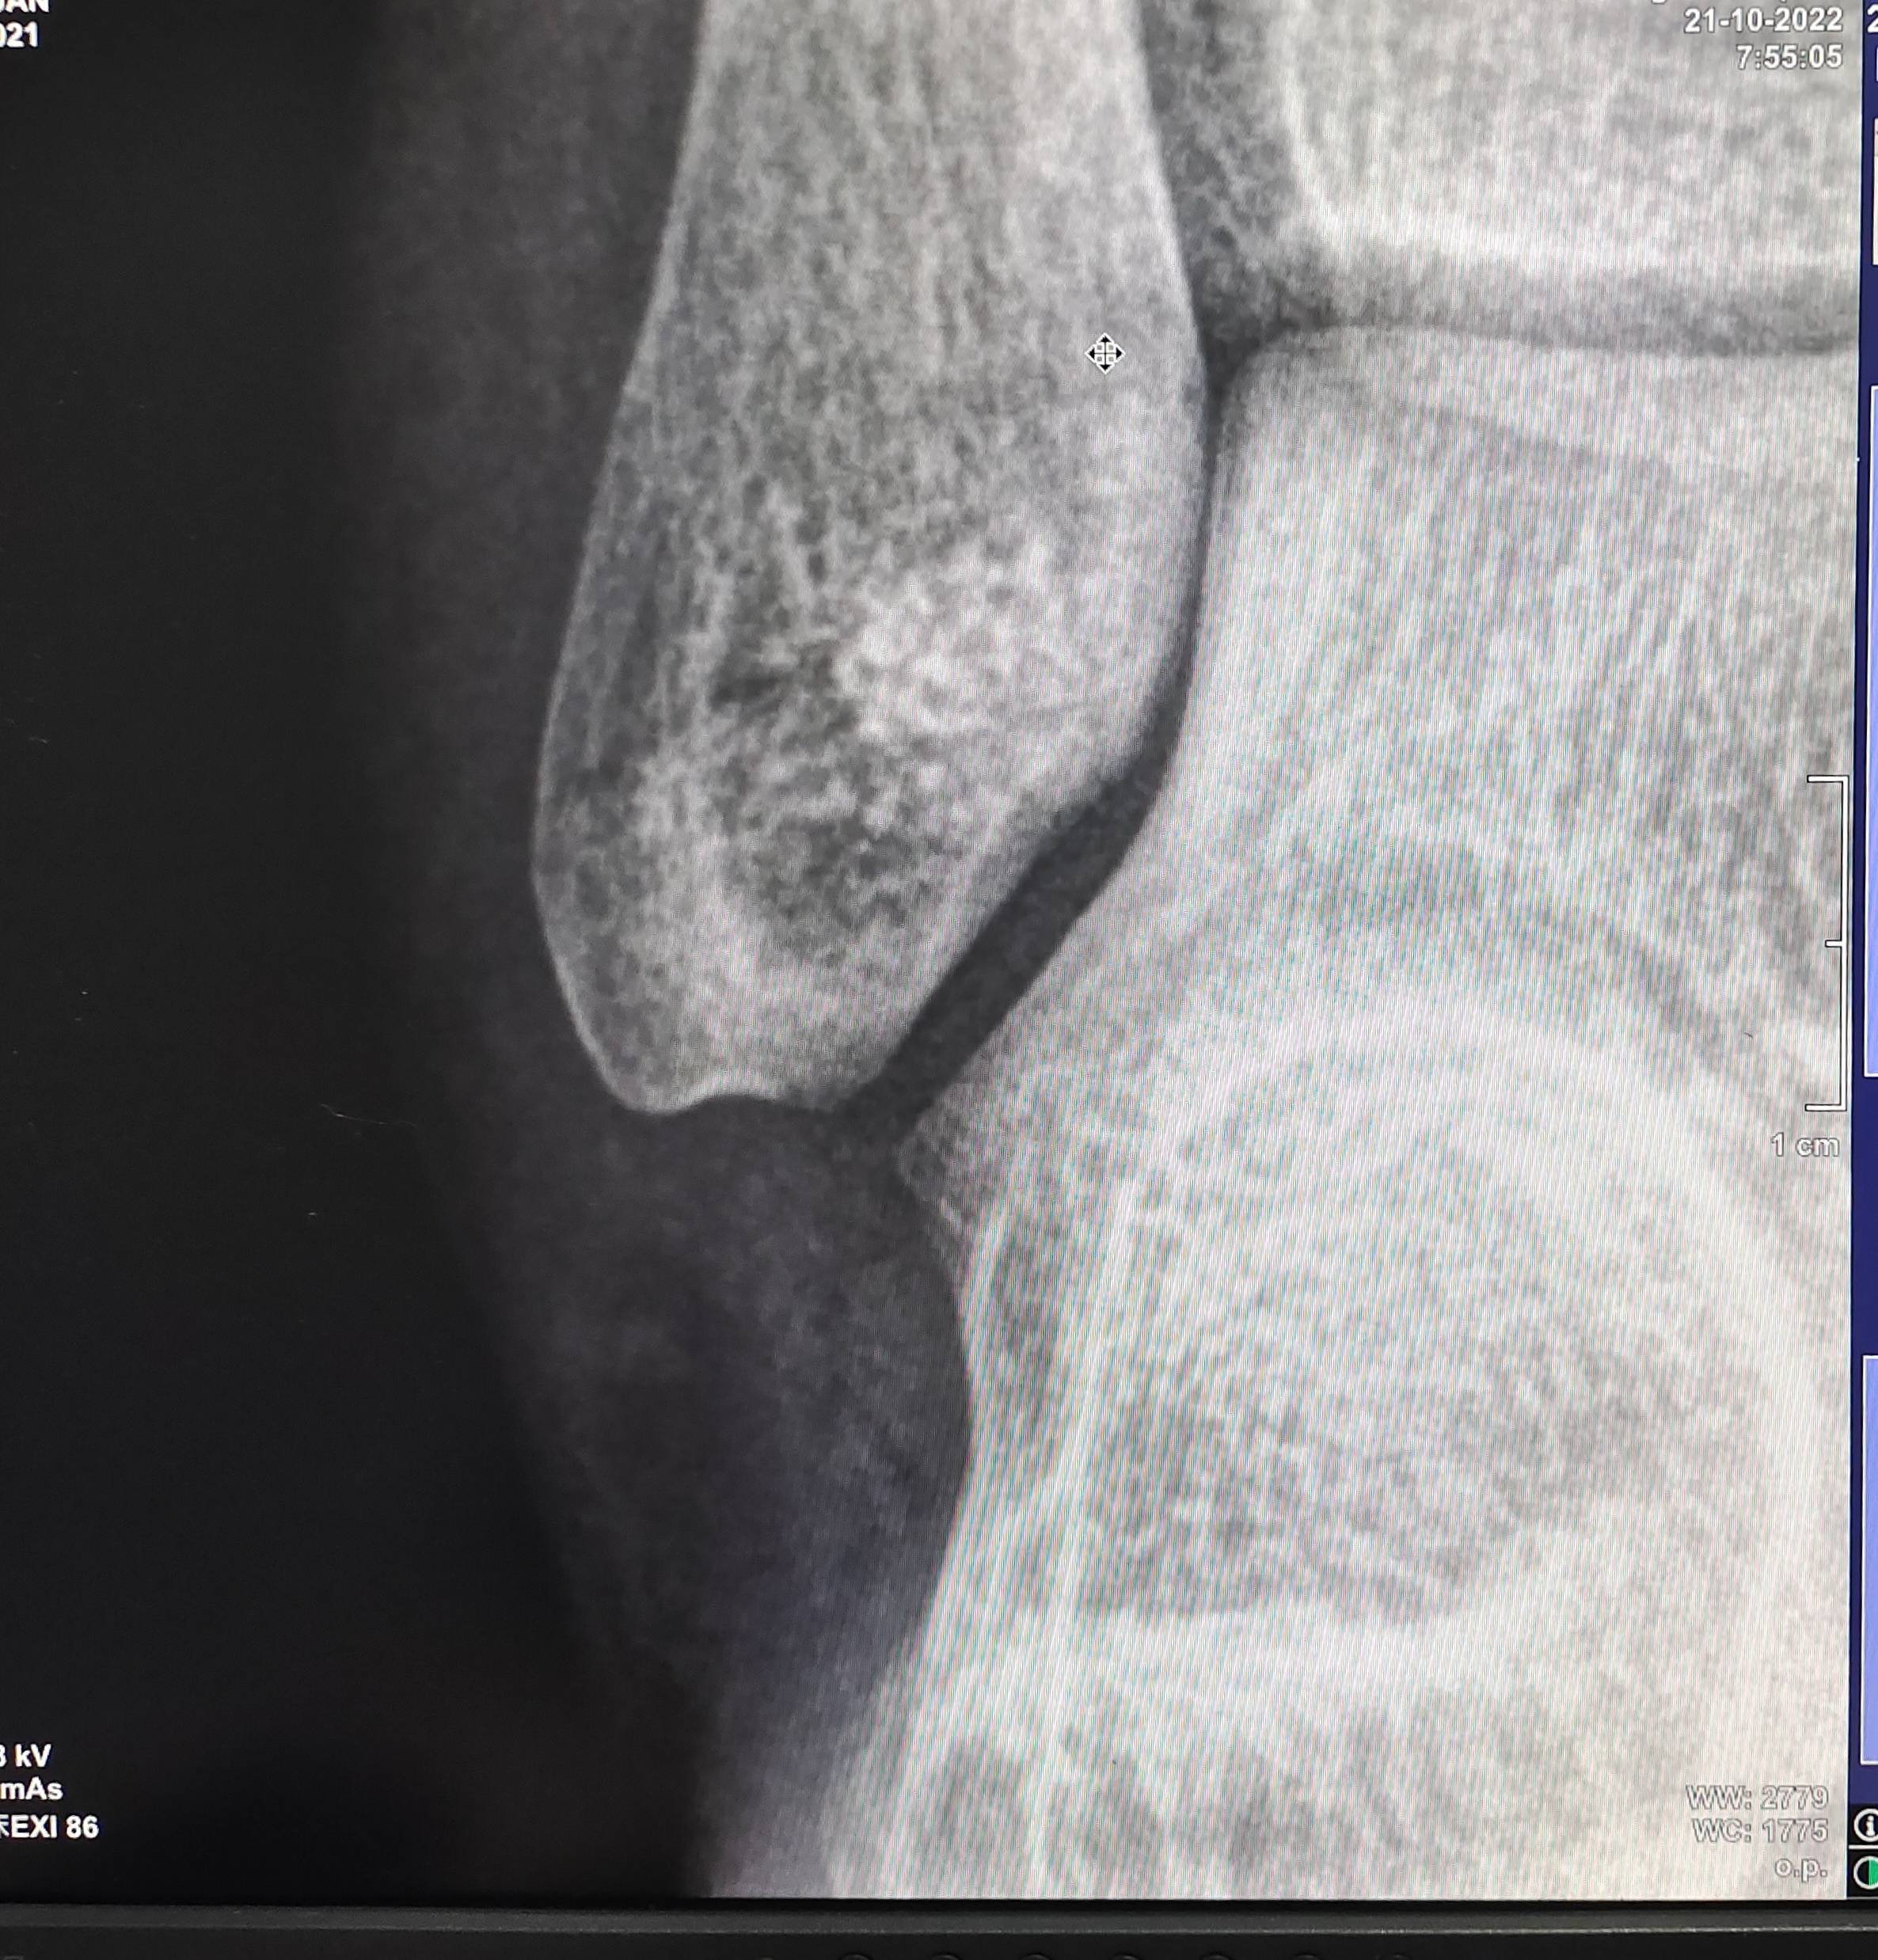

昨晚打羽毛球,崴脚了。今天早上拍了DR和CT,哦豁,骨折了。

现在已打石膏。